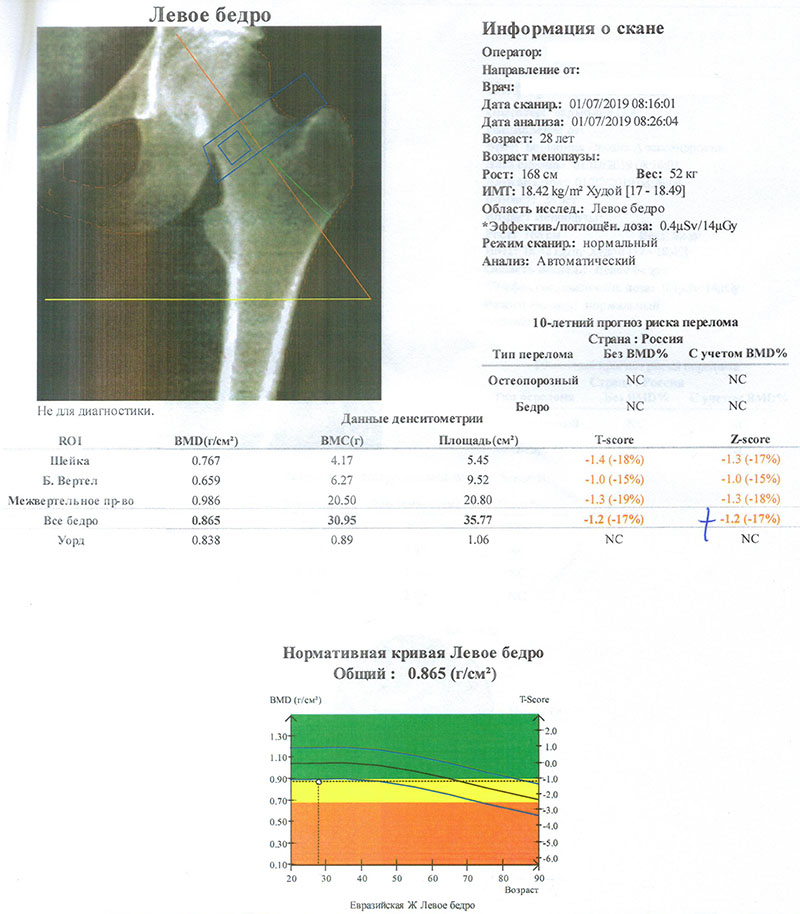

Иллюстрации и снимки, связанные с остеопенией шейки бедра